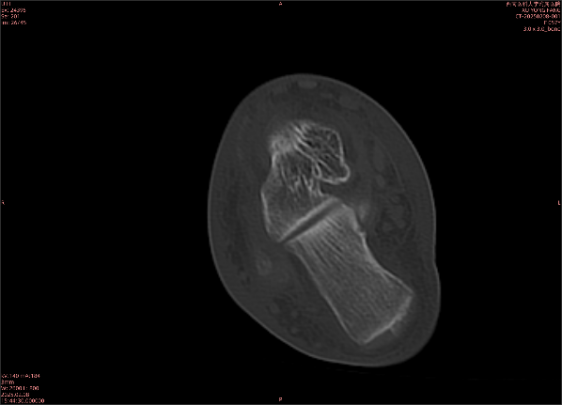

為什么DR和CT基本無(wú)法診斷?(專(zhuān)業(yè)科普)

由于無(wú)骨皮質(zhì)中斷,尚不足以引起X線衰減系數(shù)的明顯改變,X線平片無(wú)異常征象;CT在顯示骨皮質(zhì)及軟組織異常方面明顯優(yōu)于傳統(tǒng)X線,特別是三維重建能夠有效的評(píng)價(jià)復(fù)雜骨折,骨外傷CT檢查應(yīng)用廣泛,但CT對(duì)隱性骨折的顯示亦極為有限。

舉例圖像

圖2

專(zhuān)業(yè)解釋看不懂沒(méi)關(guān)系,大家看圖1和圖2就可以了,這是同一個(gè)患者跟骨的磁共振和CT圖像,圖1的紅色箭頭指示的黑線就是磁共振圖像顯示的骨折線,一目了然。而對(duì)比圖2的CT圖像上并未顯示異常。